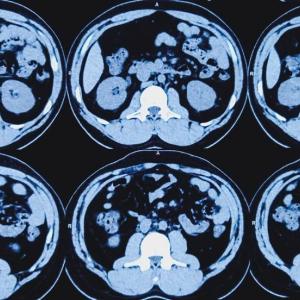

The deep learning-based model is able to detect cancerous masses in the pancreas by examining non-contrast CT scans, a more efficient form of medical imaging used worldwide with a lower dose of radiation than contrast CT scans.